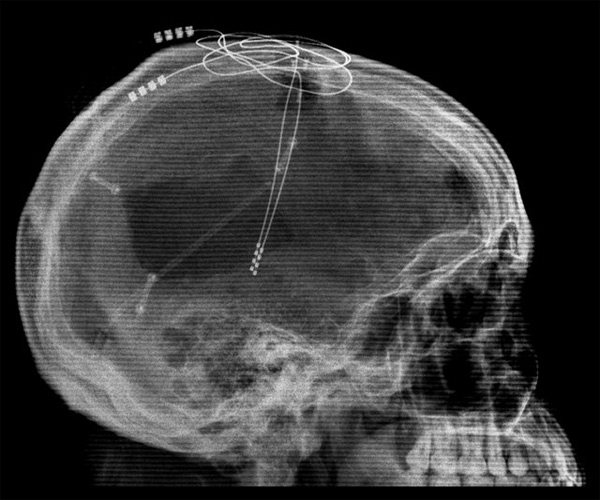

Применение магнитной стимуляции, как и транскраниальная стимуляция постоянным током (tDCS), представляют собой неинвазивные методы воздействия, которые помимо очевидных достоинств имеют один недостаток. Вследствие того, что источник поля располагается на поверхности черепа, затронутым оказывается лишь небольшой слой коры, дальше которого стимуляция не оказывает никакого влияния. Однако в мозгу существуют структуры, находящиеся достаточно глубоко, и подача электрического тока на них также приводит к удивительным и благотворным для человека результатам. Чтобы добраться до этих структур, ученые используют метод глубокого вживления электродов в ткань мозга.

Как позже показали томографические исследования, некоторые важные участки коры остались нетронутыми, но не функционировали. Это обстоятельство заинтересовало ученых. Они предположили, что в результате травм был отключен механизм, активирующий кору. Ключевая роль здесь принадлежит таламусу — структуре, в которой происходит обработка и интеграция практически всех сигналов, идущих в кору большого мозга от спинного, среднего мозга, мозжечка и базальных ганглиев. По мысли медиков, если подвергнуть электростимуляции ядра таламуса, это может привести к пробуждению сохраненных участков коры. Однако таламус находится глубоко в мозгу, поэтому никакая неинвазивная техника до него не достанет. Единственная возможность — внедрить электроды хирургическим путем.

После долгих обсуждений, касающихся в основном этических коллизий, возникших в связи с оперированием человека без его согласия, процедура была исполнена. Практически сразу же, в первые два дня работы электродов, состояние пациента заметно улучшилось. Он стал держать глаза открытыми продолжительное время и отзываться на голоса, поворачивая голову. Ученые, однако, были вынуждены сделать паузу на 50 дней, чтобы удостовериться, что улучшение не является неизвестным эффектом хирургического вмешательства. Затем на протяжении 18 недель таламус стимулировали различными сочетаниями частоты и продолжительности возбуждений, дабы найти наилучший вариант.